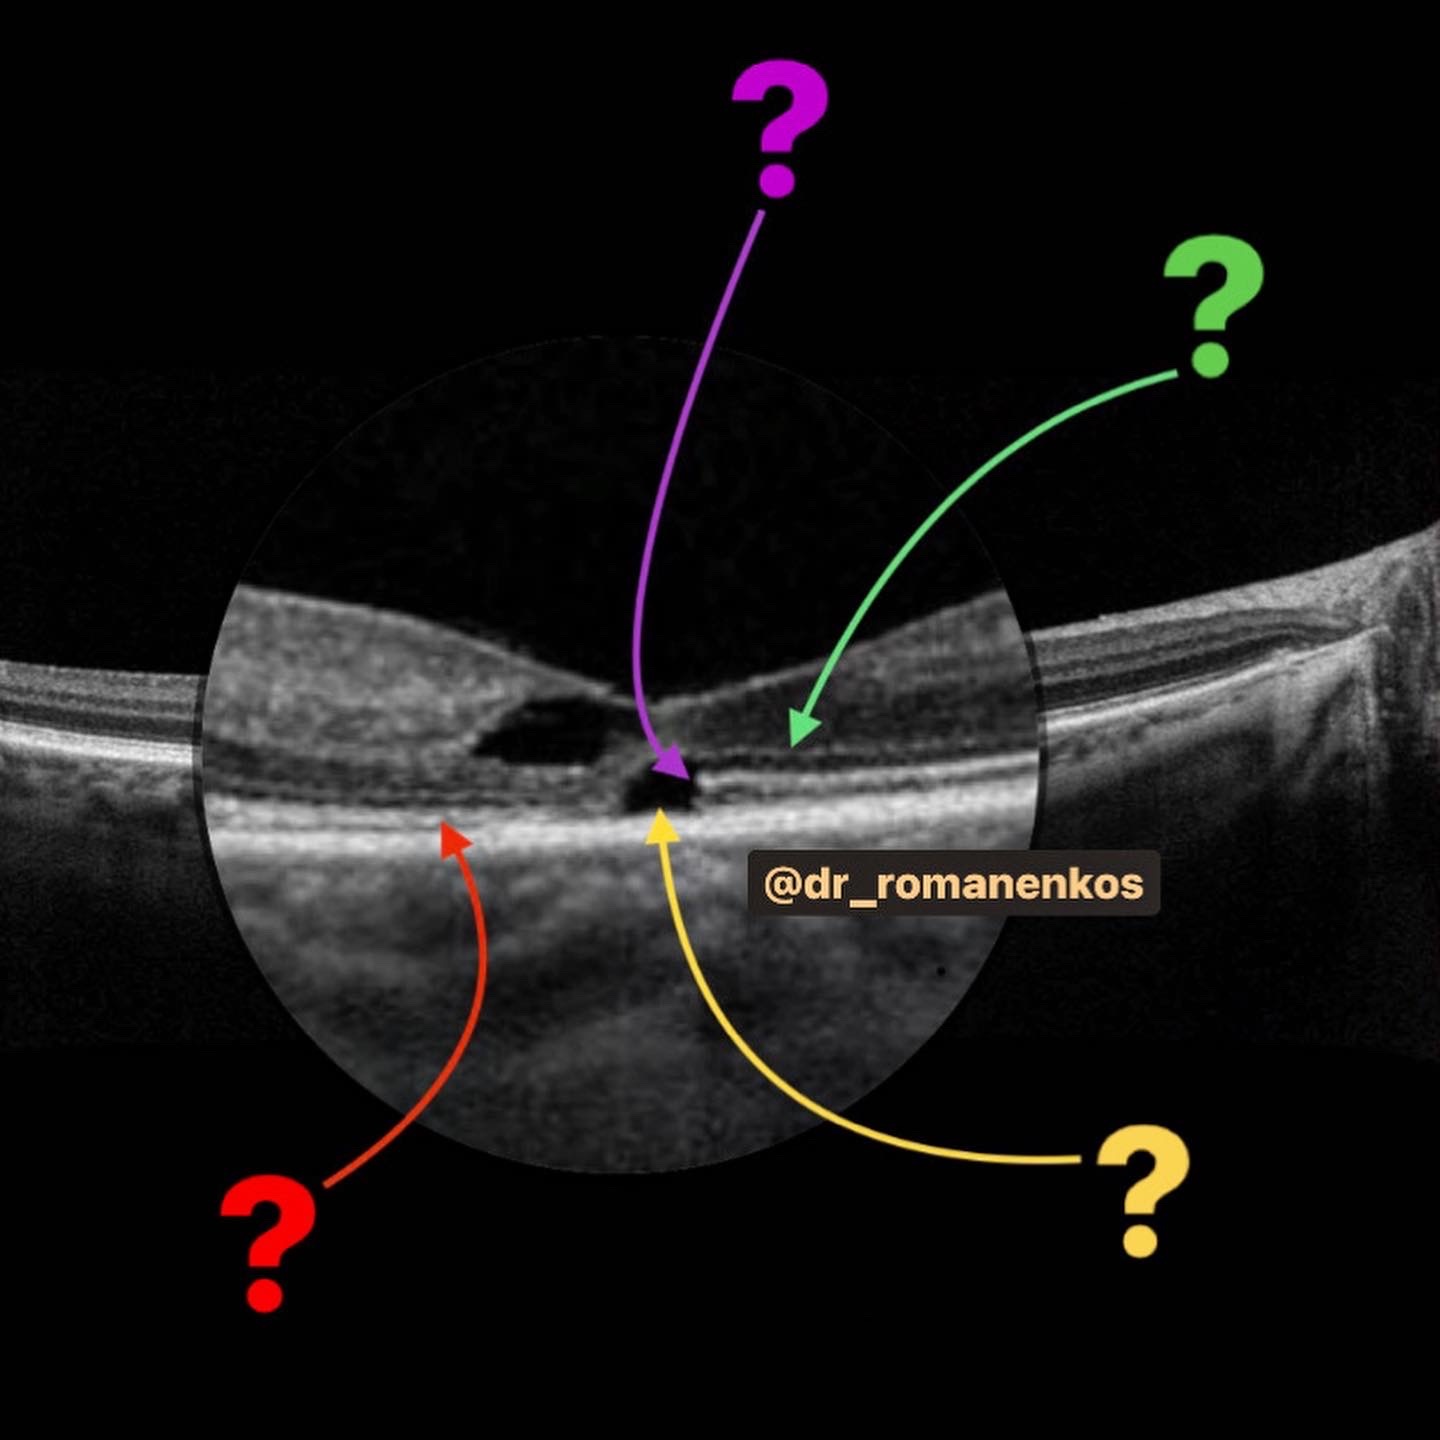

Нам необходимо четкое умение определять анатомические ориентиры, узнавать структуры на ОКТ и видеть патологические изменения - и у НАС оно появится:

3. В стиле @dr_romanenkos проработаем ОКТ-АНАТОМИЮ глаза;

4. Мы разберем все общие признаки патологий, которые встречаются в оптической когерентной томографии;

Нам необходимо четкое умение определять анатомические ориентиры, узнавать структуры на ОКТ и видеть патологические изменения - и у НАС оно появится:

3. В стиле @dr_romanenkos проработаем ОКТ-АНАТОМИЮ глаза;

4. Мы разберем все общие признаки патологий, которые встречаются в оптической когерентной томографии;

Окончив курс "Оптическая когерентная томография.НАЧАЛО" мы обрели умение видеть признаки патологии на сканах OCT.

Настало время усложняться и углубляться!

1. Дифференциальной диагностике заболеваний заднего отрезка глаза;

2. Умению видеть признаки стадий и активности заболеваний;

- видео, сканы ОКТ с обозначениями, фото глазного с разбором на детали, аудисопровождение, текст и, конечно, ОБУЧАЩИЕ ТЕСТЫ